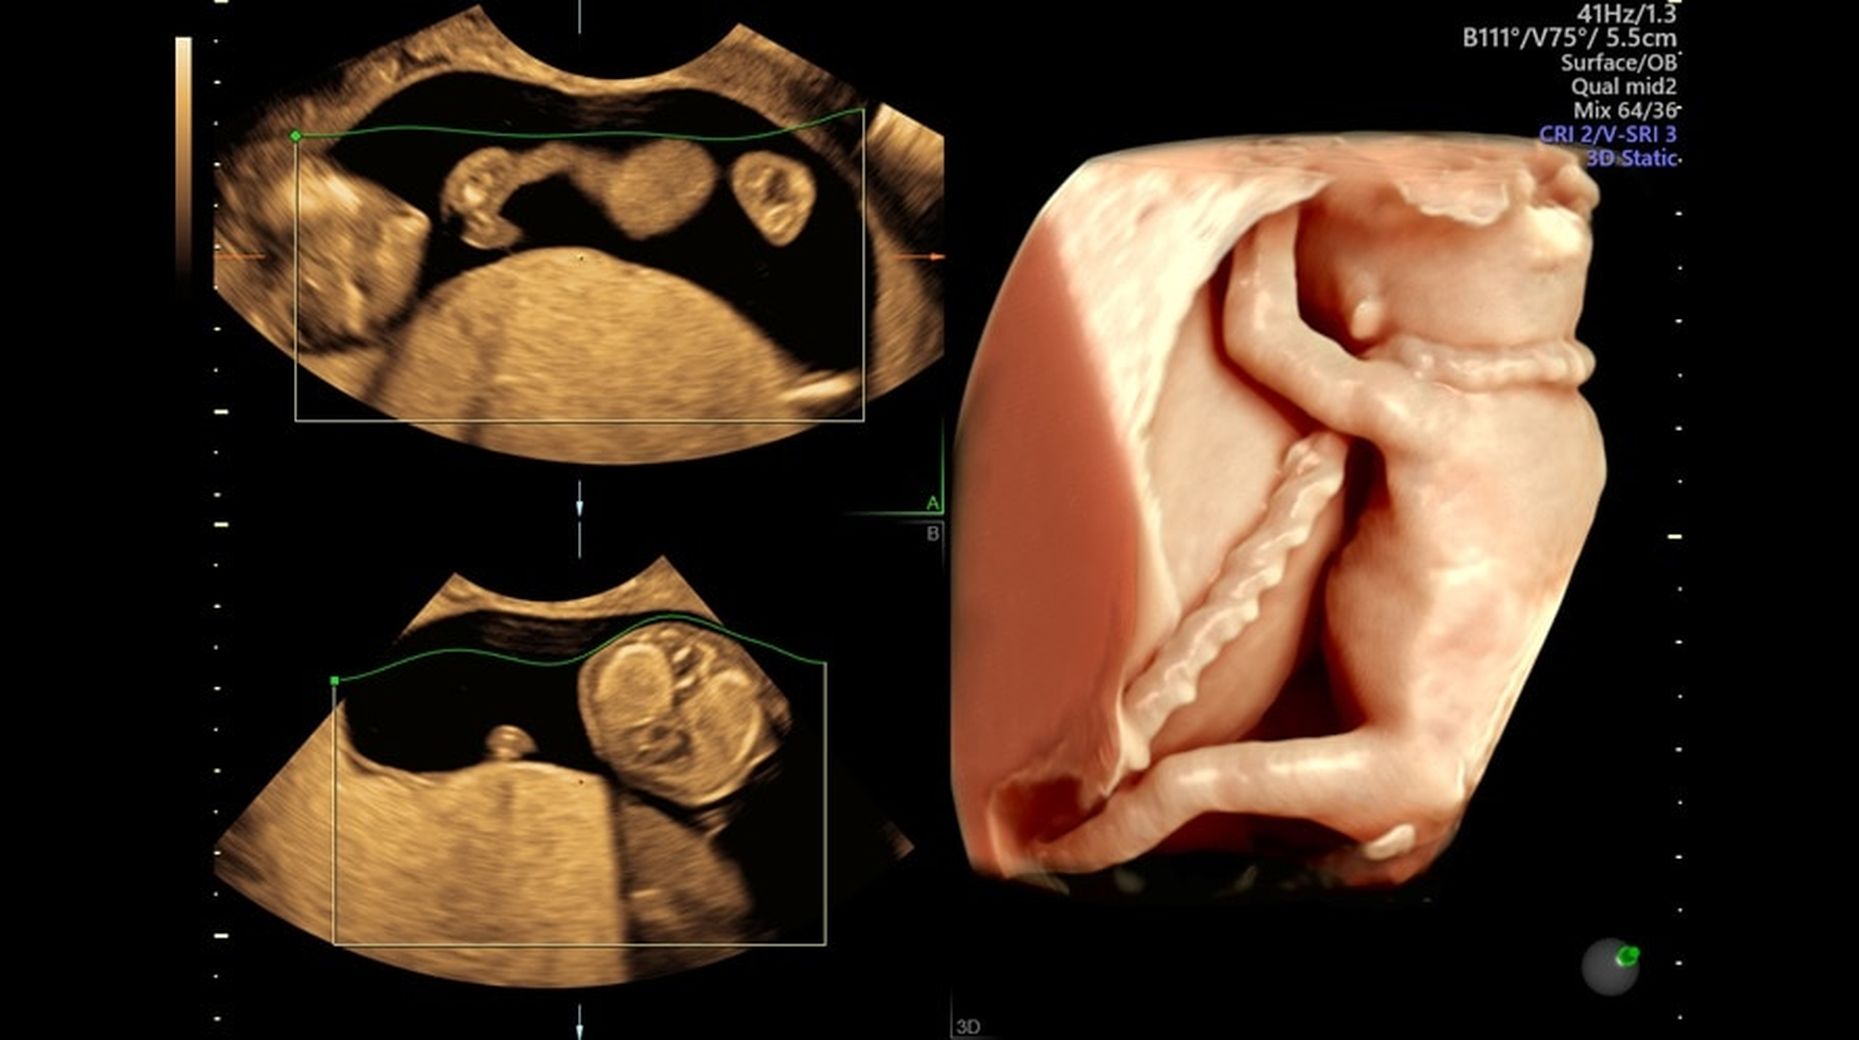

Узи voluson e10

Узи voluson e10 134 фото